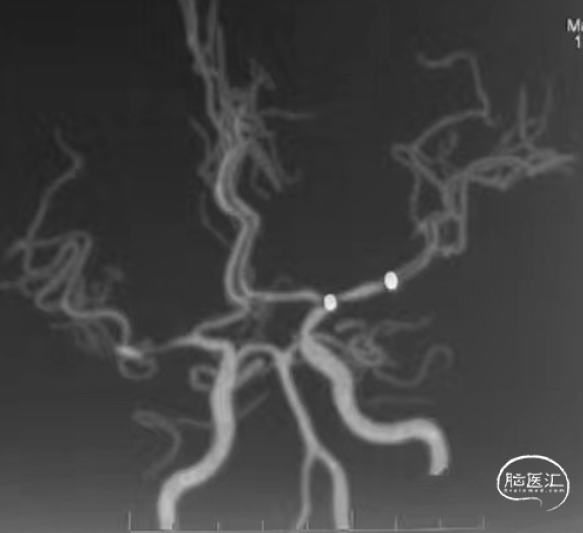

释放自膨式闭环支架 4*16mm后造影。

最后正侧位造影。

正位

侧位

术后CTA复查。